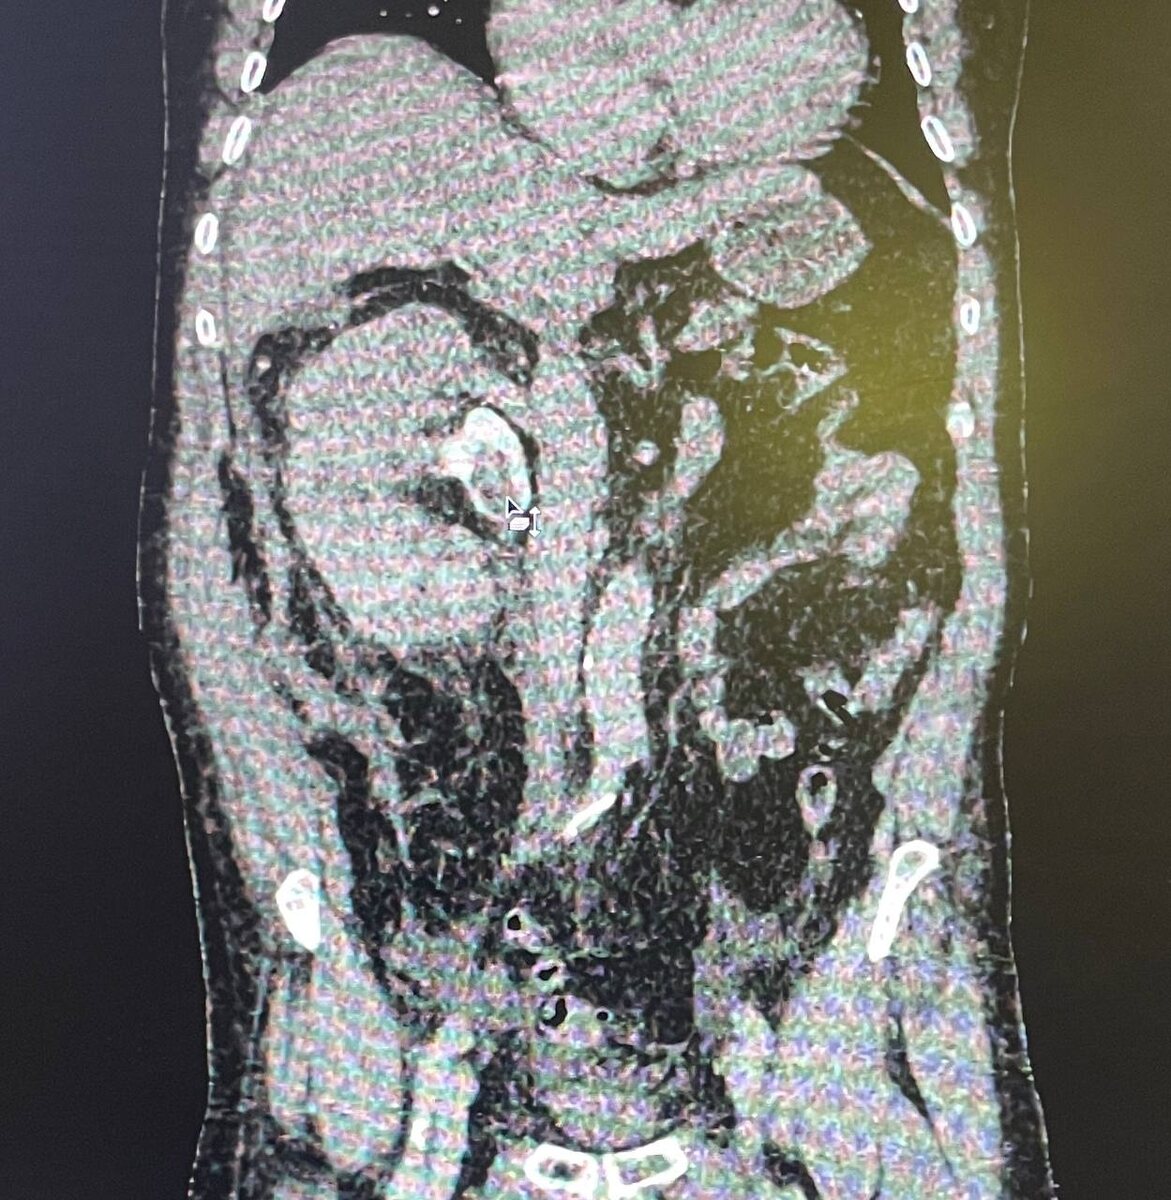

Во II, III сегментах правой почки определяется крупное гиперваскулярное образование единственной правой почки (1 фото, в анамнезе агенезия левой почки), с инвазией в ЧЛС (2 фото), с опухолевым тромбозом почечной вены, с пролапсом опухолевых масс в просвет нижней полой вены (3 фото). Отёк паренхимы правой почки со снижением её выделительной функции. Каликопиелоэктазия с геморрагическим содержимым в чашах и лоханке. Остаточная забрюшинная гематома справа (образовалась после попытки установки нефростомы, опухолевые массы в ЧЛС помешали манипуляции, оставленную нефростому можем видеть вдоль заднего листка фасции Героты - выполняет функции дренажа сформировавшейся забрюшинной гематомы).

Также определяется гиперваскулярное образование в латеральной ножке правого надпочечника (mts?, 4 фото). Диффузные изменения печени. Липоматоз поджелудочной железы. Асцит. Дивертикулёз сигмовидной кишки без признаков дивертикулита. Атеросклероз брюшного отдела аорты и подвздошных артерий. ДДЗП.